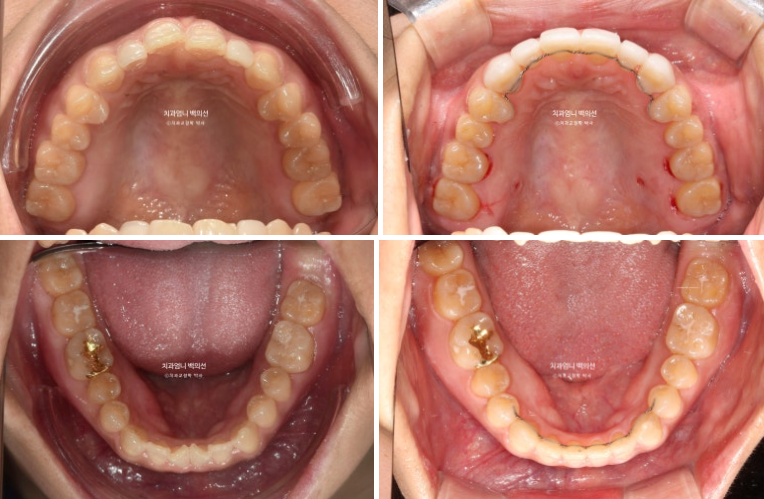

치료시작 1년 후 모습입니다.

배열 교합 등 모든게 양호해서 마무리 교정 5개월을 더 진행한 후, 이제 무삭제 라미네이트 젤라미 치료 준비에 들어갑니다.

24.10

치료시작으로부터 1년 5개월 후 모습입니다. 먼저 위 장치 다 떼고 피팅준비를 합니다.

파란 화살표 측절치는 환자분이 오래전 했던 왜소치 라미네이트입니다.

이 라미네이트도 제거 후 재제작 하기로 합니다.